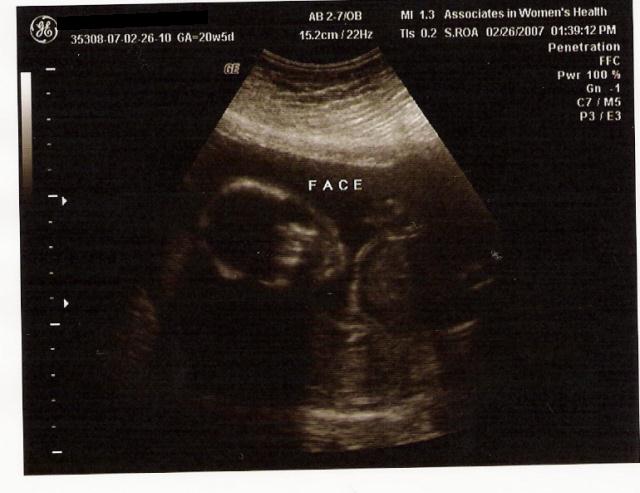

OMG! I can't believe it. I'm half way through this pregnancy! ANNNNNND....

IT'S A GIRL!!!

The pic is of her "face". Not that you can really see anything other than the skull...I so CAN NOT afford that 4D thing. Would be cool though. They're just damned expensive.